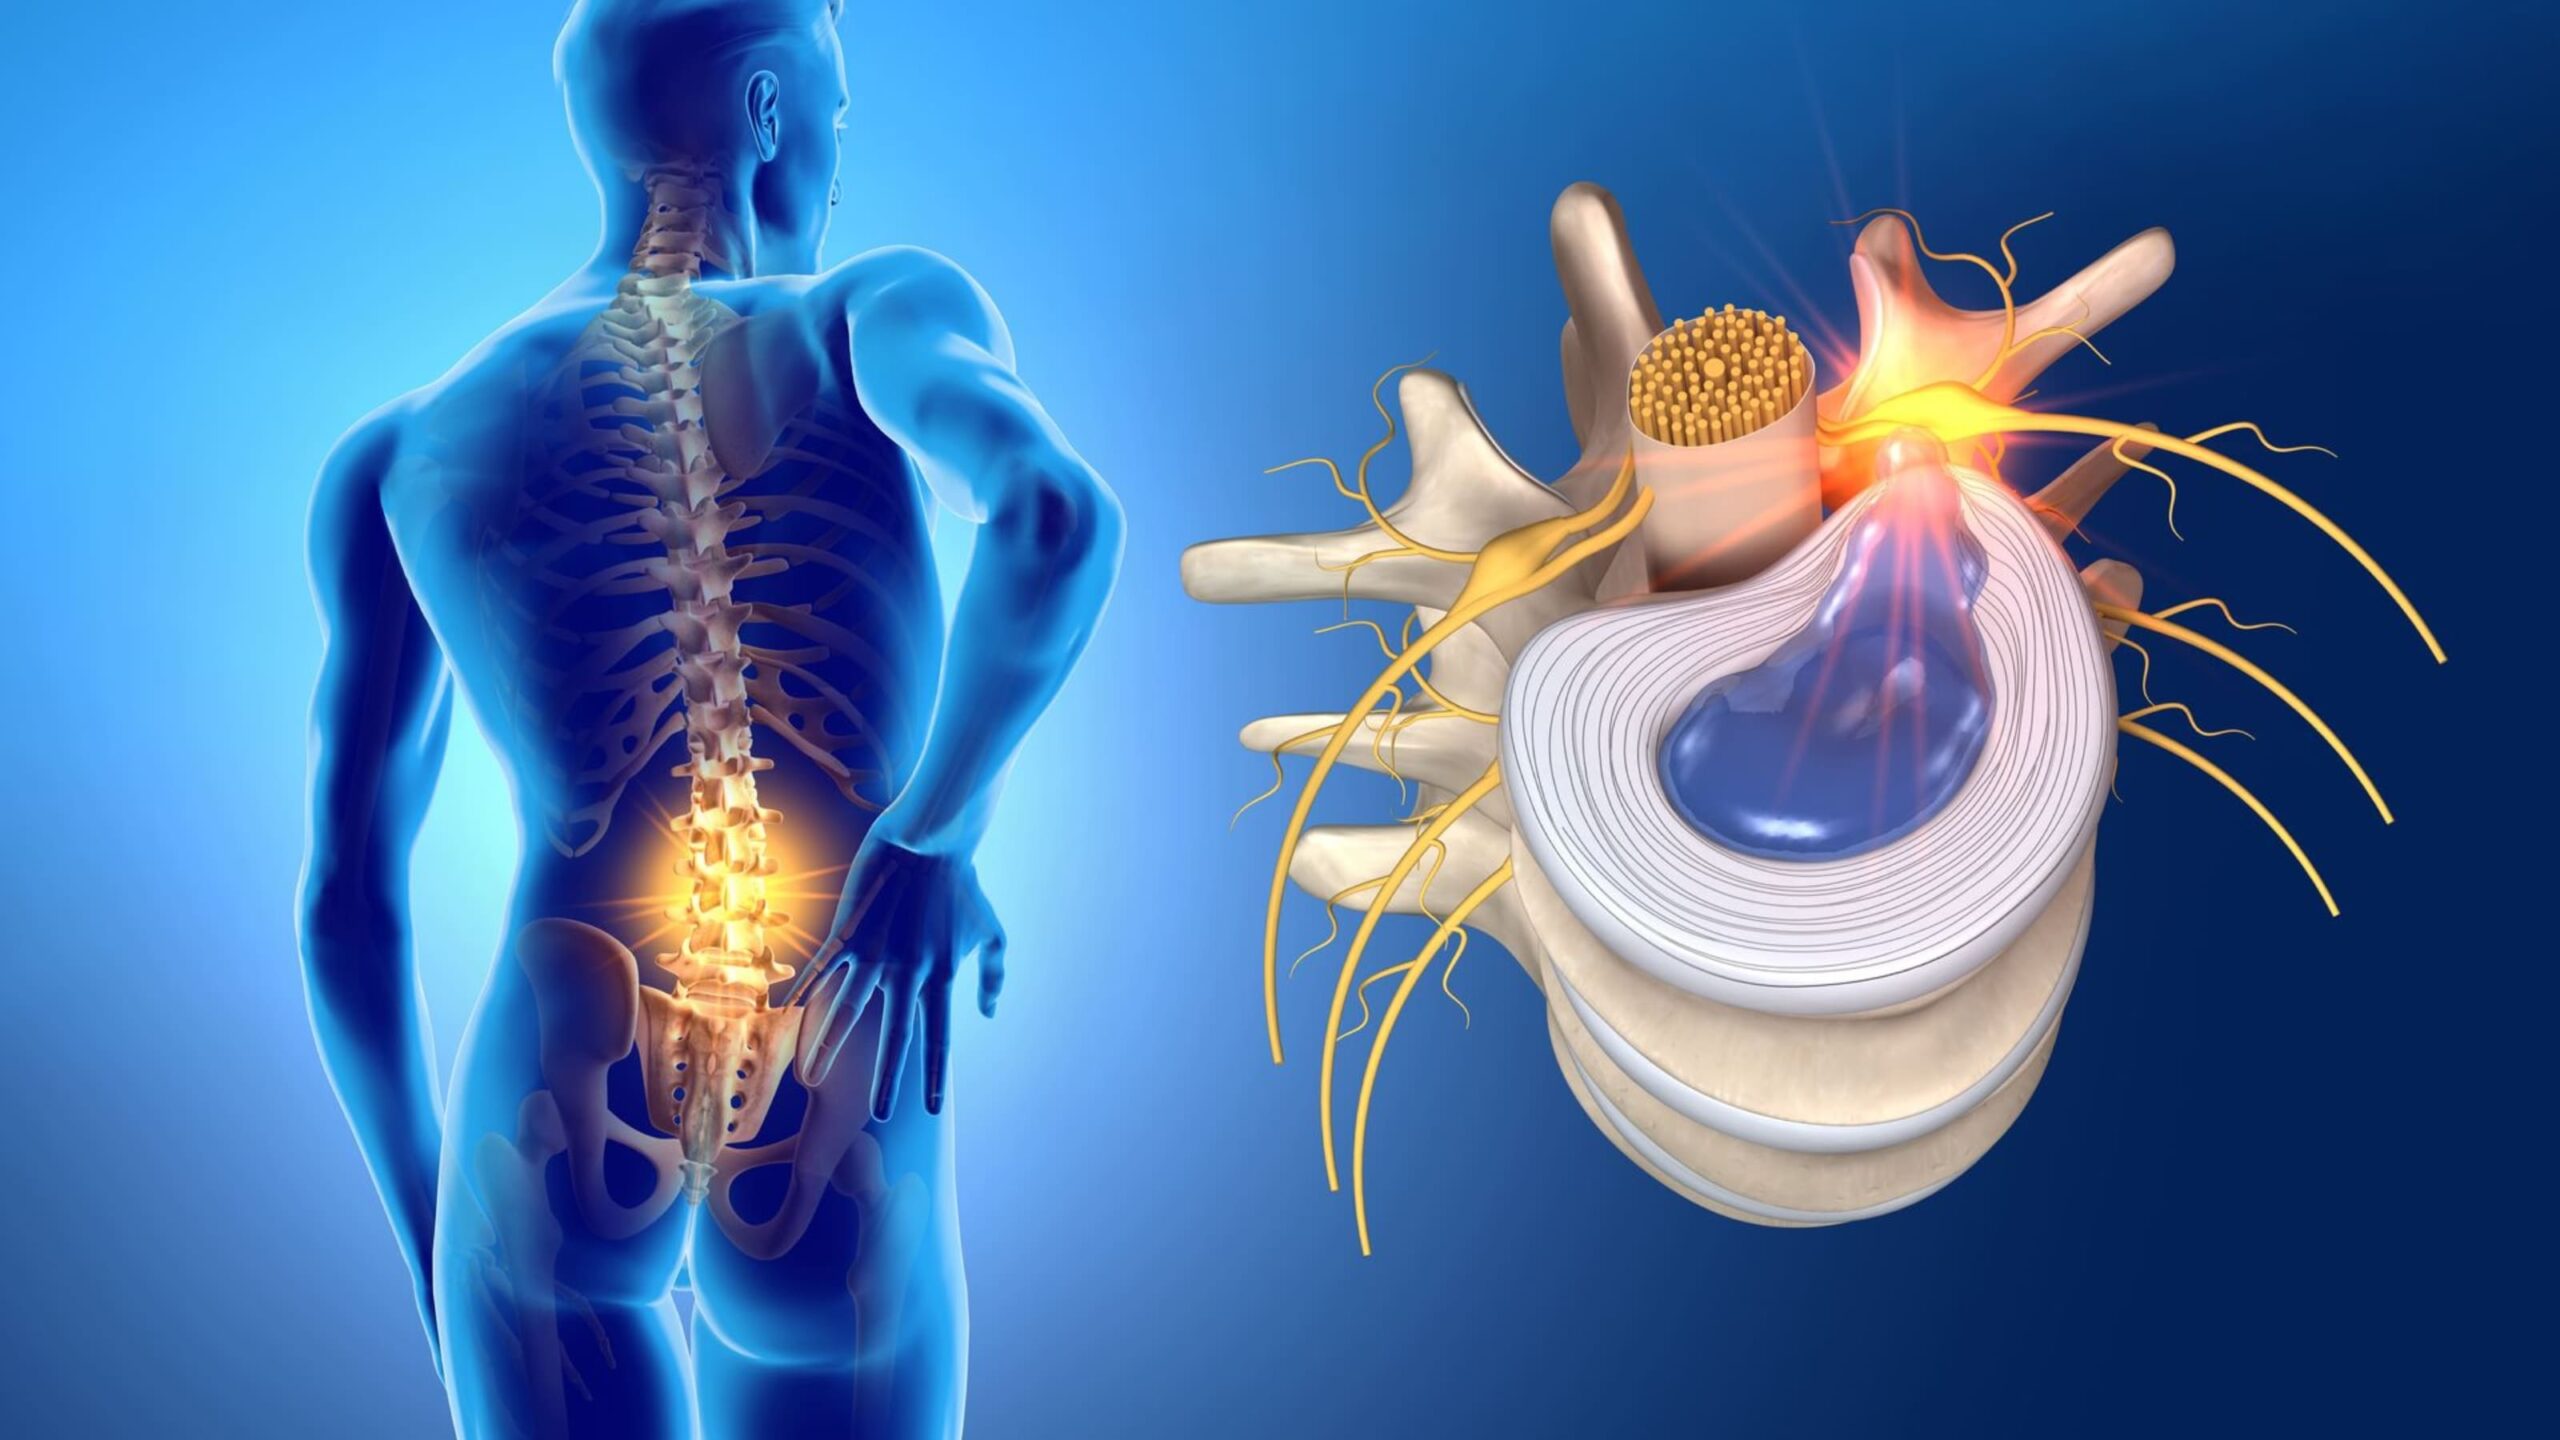

Hérnia de Disco Agendar consulta A hérnia de disco é uma condição comum que afeta a coluna vertebral e pode causar dor intensa, limitação de